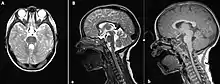

(A) MRI Brain, axial T2 sequence showing enlarged superior cerebellar peduncles and vermian hypoplasia resulting in characteristic "molar tooth" appearance; (B) MRI Brain, sagittal T2 (a) and T1 (b) sequences showing vermian hypoplasia, predominantly at the superior aspect.

The disorder is characterized by absence or underdevelopment of the cerebellar vermis and a malformed brain stem (molar tooth sign), both of which can be visualized on a transverse view of head MRI scan.[17] Together with this sign, the diagnosis is based on the physical symptoms and genetic testing for mutations. If the gene mutations have been identified in a family member, prenatal or carrier diagnosis can be pursued.[4]